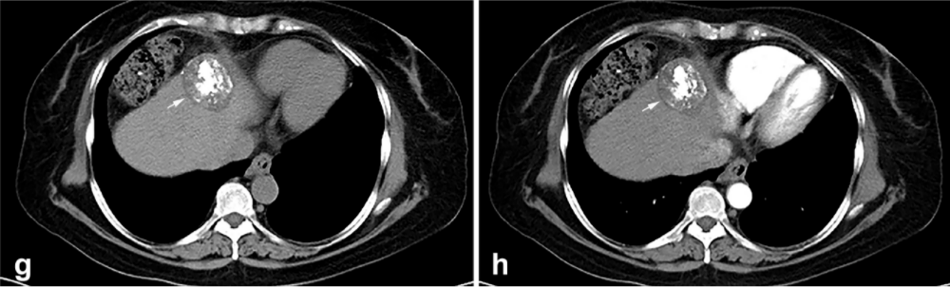

② 冷冻消融后 1 个月患者的增强 CT 显示HCC获得缓解。

③ 总生存曲线和局部肿瘤进展曲线:冷冻消融后中位生存时间为 27.3 个月,中位局部肿瘤进展时间为 20.9 个月。